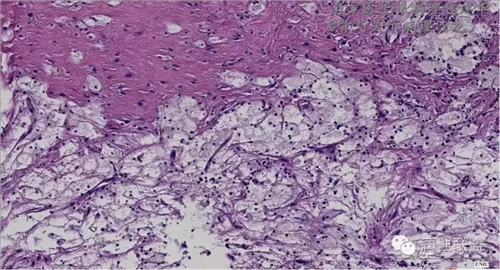

来源于组织细胞的相似性骨病ECD vs RDD 看图说话

病例由南方医华银病理魏建华提供,致谢。